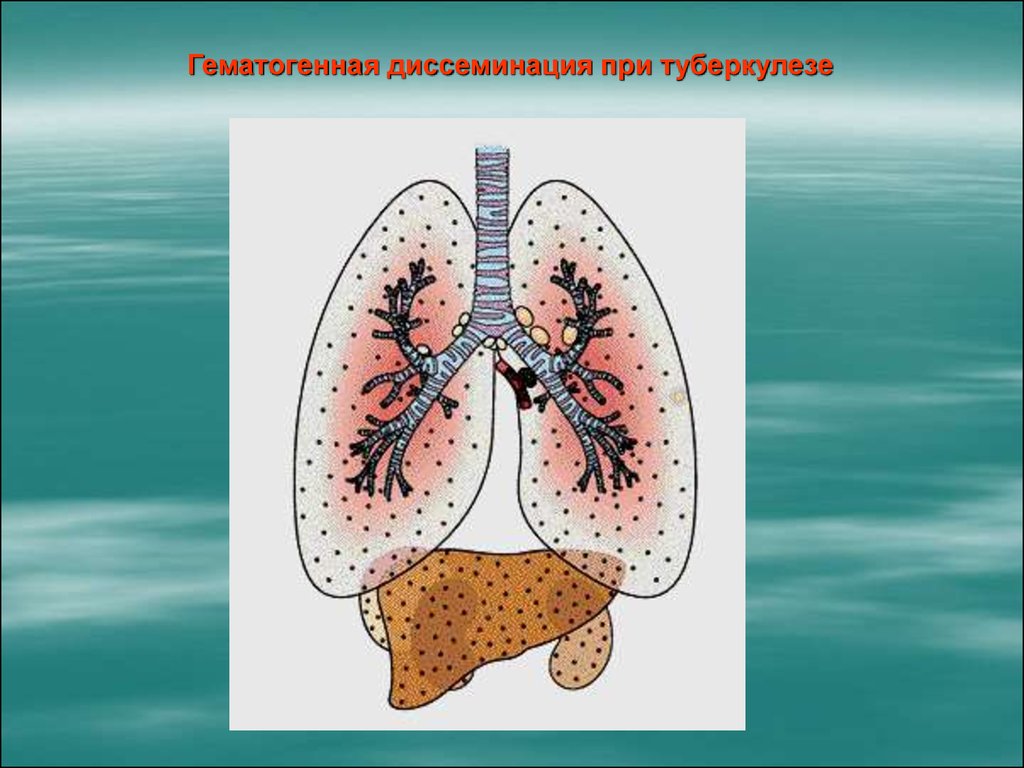

В клинической картине острого гематогенно диссеминированного туберкулеза преобладает